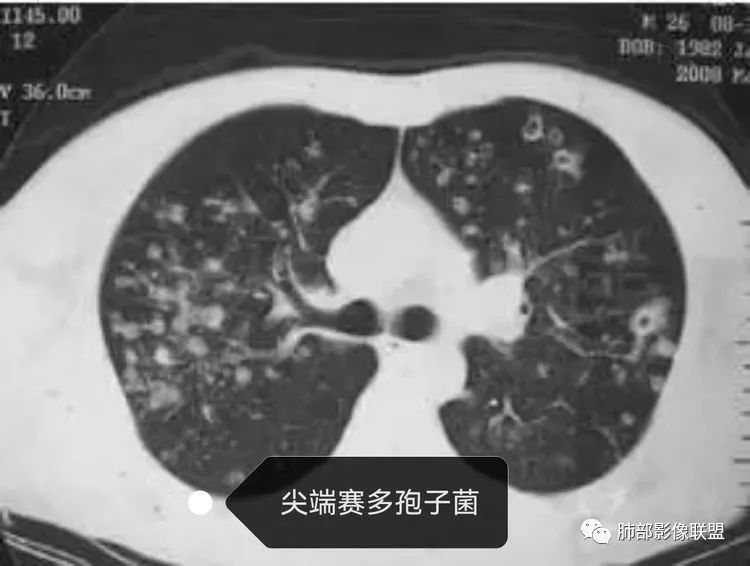

白细胞不高的金葡,病灶边缘模糊

同样是血播的,金葡与肺克比较,金葡更趋于磨玻璃,肺克更趋于实变。给肝脏层面,作者的意思,就是告诉你没有肝脓肿。

从放射科来讲:尖端赛多孢子菌和SPE阴影分布特点,如气道、还是随机分布,影像是否有区别?理论上尖端赛多孢子菌应该是气道,而血播金葡是随机,可惜我掌握不好。

| 血管来源 |